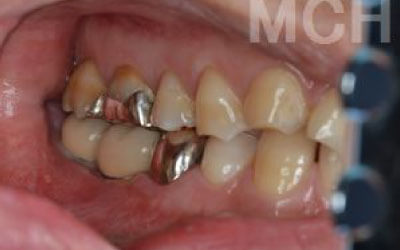

最も大きな違いは、前後の歯の寿命が変わることです。

ブリッジは、抜けた部分の前後の歯を大きな虫歯と同じくらい削る必要があります。

さらに、抜けた歯の力を前後の歯が負担するため、ブリッジを支える歯には常に1.5倍の力がかかります。

1)ブリッジ

2)歯を大きく削る+支えの歯に1.5倍の力がかかる

3)前後の歯の寿命が著しく減る

ブリッジの支えの歯は、データでは10年以内に68%が抜歯になります。